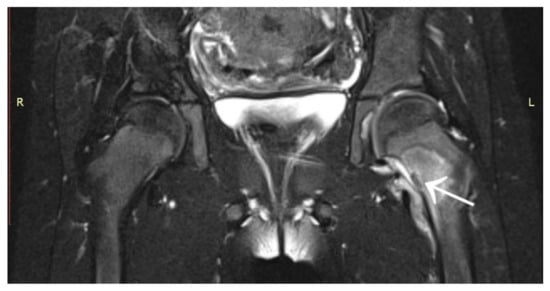

3.1. Case 1: OO Masking as Femoroacetabular Impingement (FAI)